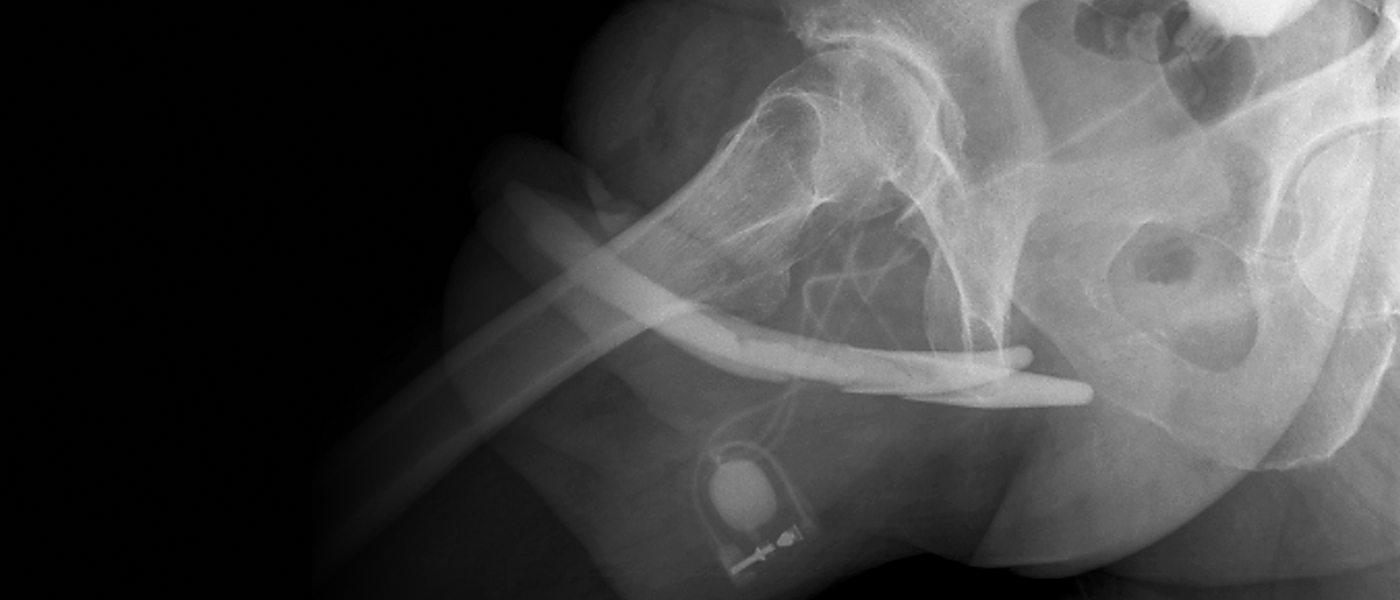

손상 정도에 따라 이물질 제거술과 함께 조직 재건술이 필요할 수 있으며 전문의 상담이 필수입니다.